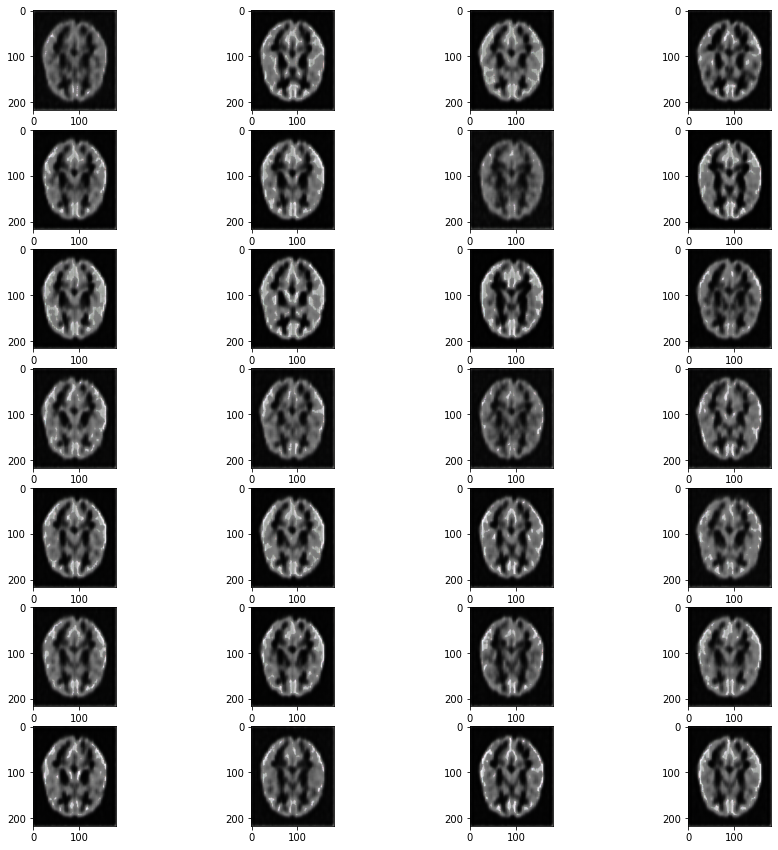

One of the main aspects of our project is MRI Image Synthesis. In this, we convert T1-Weighted images into T2-Weighted images. Along with this, our other model helps by generating Segmented Brain MRI images to show the distribution of white matter.

So we have created two models, one for Image synthesis and the other does Segmentation. Both works on generating images. We have implemented VAEs to achieve the purpose.